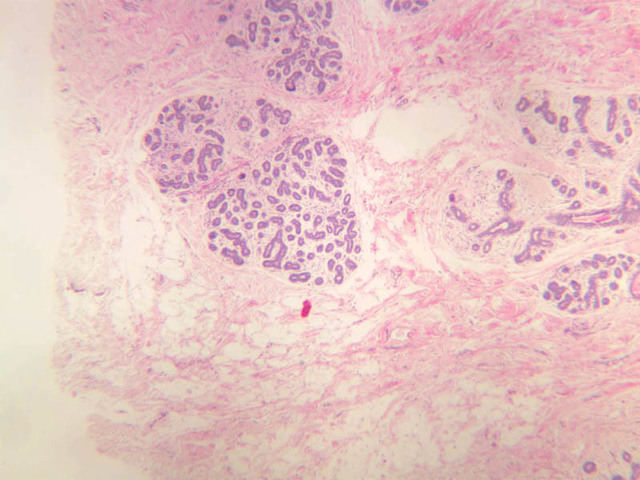

The mammary gland in its active state is a compound tubuloalveolar gland (slide A-92 [10x, 20x, 40x-labeled] [2.5x, 10x, 20x, 40x]; A-94 [2.5x, 10x, 20x, 40x]). At this time, the gland is predominantly glandular tissue. Each alveolus is lined by a simple cuboidal epithelium. At the base of these cells, and within the alveolar basal lamina, are the stellate-shaped myoepithelial cells that are highly contractile and function to facilitate milk ejection.